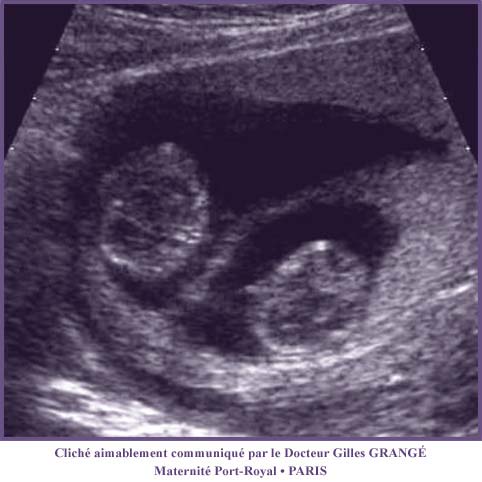

Figure 5 : Echographie d'une grossesse gemellaire